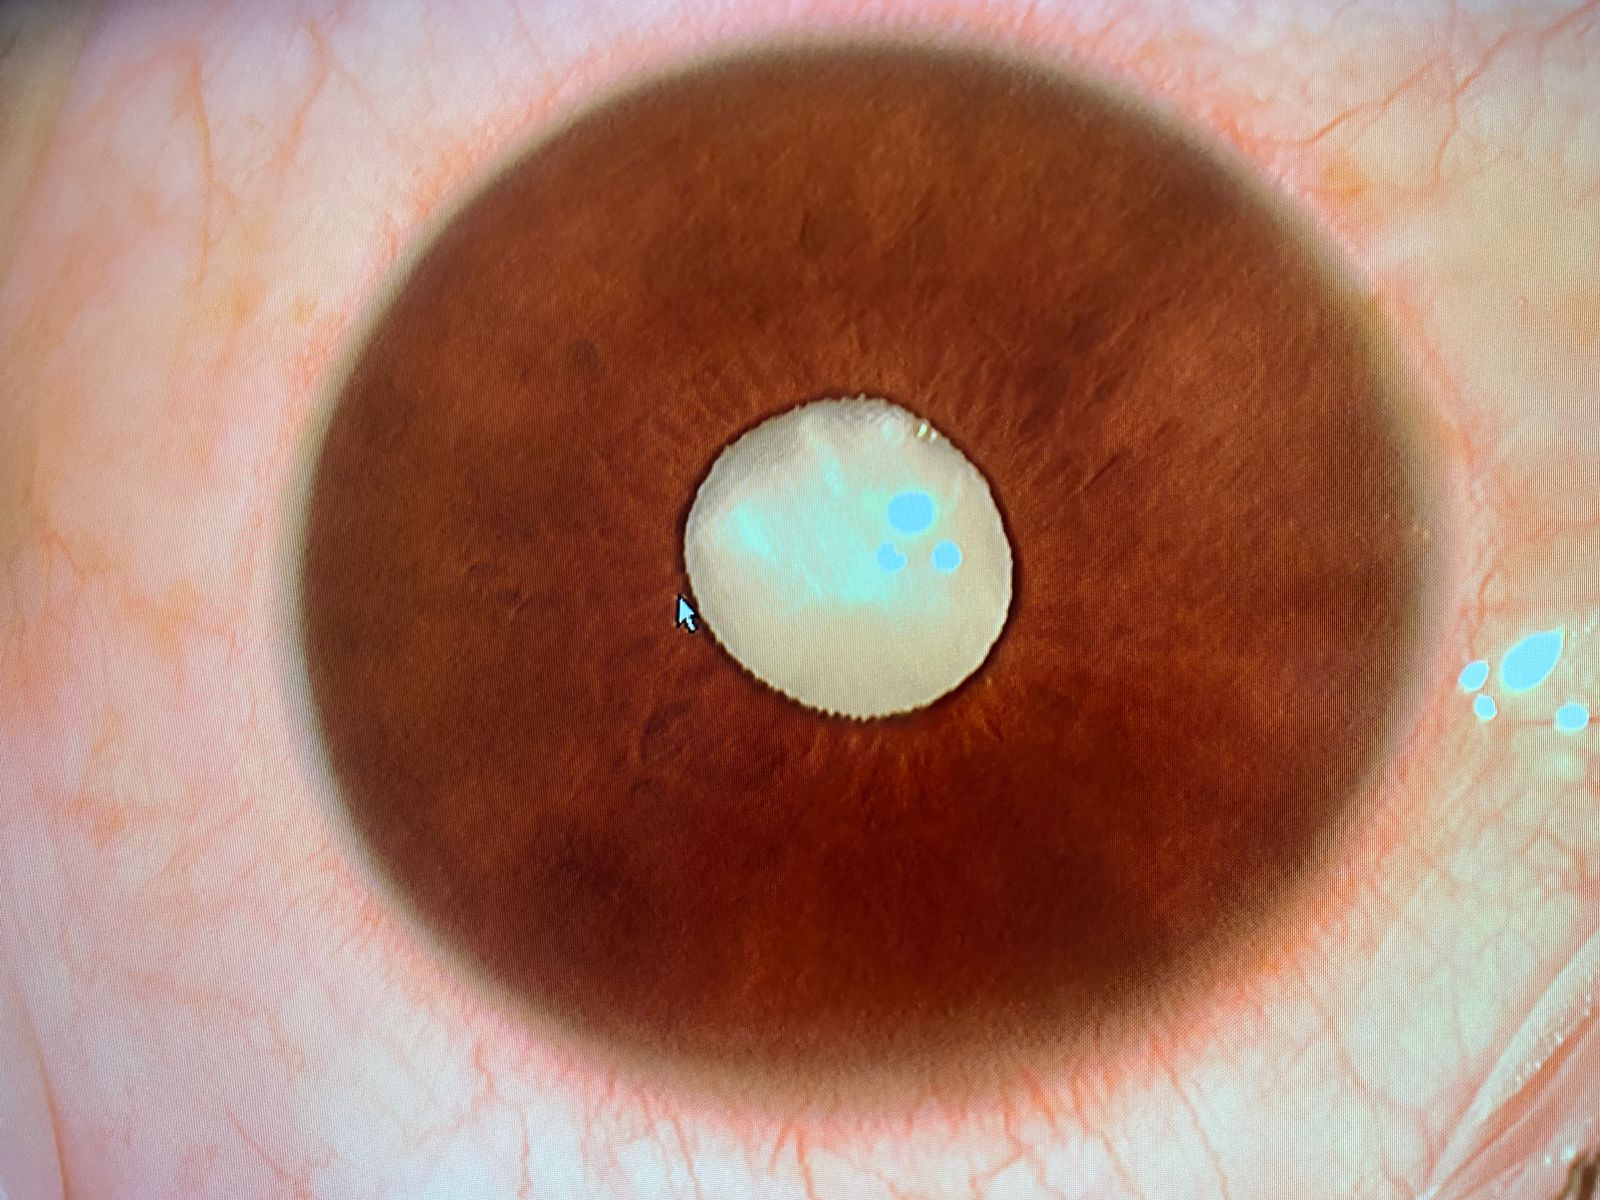

O deputado federal Eduardo Velloso realizou nesta segunda-feira (6) uma cirurgia que devolveu a visão ao senhor Antônio Valdeir, de 37 anos, morador de Brasiléia. O paciente estava sem enxergar dos dois olhos, há dois anos de um e há dois meses do outro, e dependia de uma guia para se locomover. O encontro entre Velloso e Antônio aconteceu no domingo (5), durante uma confraternização promovida pelo parlamentar, pela deputada estadual Maria Antônia e pelo ex-prefeito Deda, no município do Alto Acre.

Durante o evento, Maria Antônia apresentou o caso ao deputado, que é médico oftalmologista. Sensibilizado com a situação, Velloso se prontificou a realizar a cirurgia já no dia seguinte. Com o apoio da deputada e do ex-prefeito, o paciente foi levado até Rio Branco, onde passou pelo procedimento.

A operação foi um sucesso. Logo após o procedimento, Antônio voltou a enxergar, colocando fim a um longo período de escuridão. “É impossível descrever a emoção de ver alguém recuperar a visão. Esse é o tipo de milagre que a medicina nos permite presenciar e que dá sentido à nossa profissão e ao nosso mandato”, disse o deputado Eduardo Velloso.